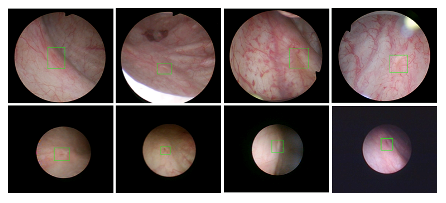

日本女优 医疗机器人研究院—深睿医疗人工智能医学视频联合实验室成立于2018年7月。PI包括来自于交大生医工学院和电院的三位教授,平台建设目标是将人工智能实时地用到临床医学中去,研究方向包括:1. 建立内窥镜人工智能辅助诊断系统,通过对病灶和解剖结构的实时识别来辅助医生更好地进行微创诊断和治疗;2. 以个性化、定量化的精准诊疗技术为研发目标,重点开展医学影像智能诊断、医学可视化及计算机辅助手术规划、AI及大数据分析在临床诊疗流程中的集成应用等方向的研发。试图利用AI技术、大数据分析技术、3D打印技术、虚拟现实及增强现实技术促进临床的影像诊断、治疗方案设计、预后预测分析等诊疗环节的智能化提升与技术变革;3. 面向运动医学康复、神经退行性疾病量化诊断,以及其他与人体运动相关的疾病诊疗、康复应用,开展视觉三维人体运动的测量、分析与识别研究,通过基于深度学习的视觉检测识别以及相关大数据分析,为相关疾病的诊疗和康复提供AI辅助。具体临床应用包括:关节镜手术术后康复指导和评估、帕金森病的量化诊断、精神疾病的量化诊断与评估、儿童异常行为分析等。

近年来,联合实验室发展了泌尿镜手术实时识别技术,人体姿态精确识别技术,另外围绕小儿先心病手术、肝癌消融手术、数字口腔诊疗的智能化提升等内容进行应用研发。